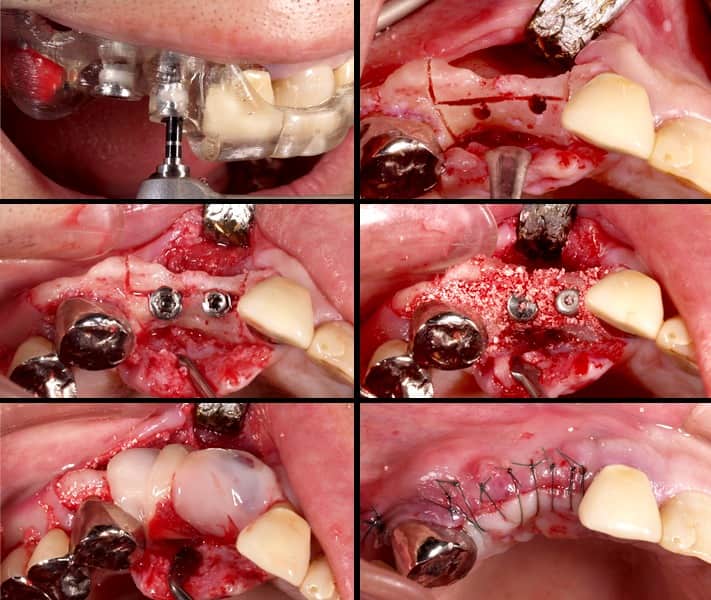

Nobel Clinician によるシミュレーション

ガイデッドサージェリー

歯肉を開くと大きく骨が吸収しているため、インプラント埋入と同時にGBR